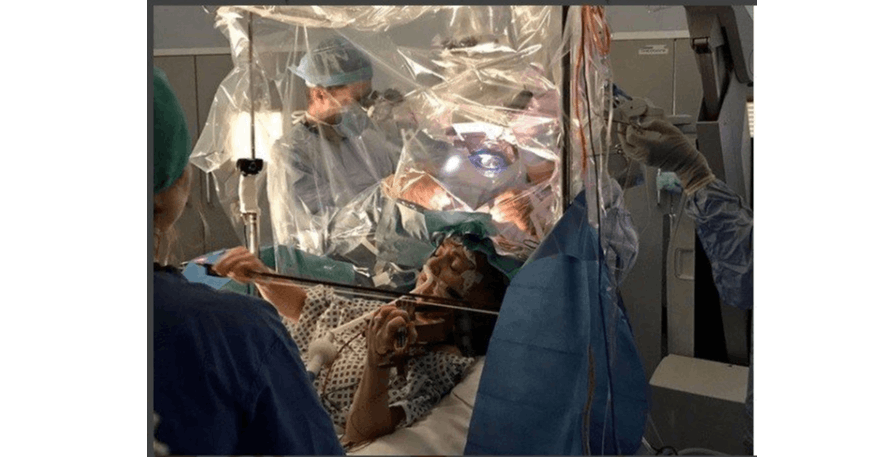

由於噪音不僅對人產生不舒適,也會造成聽力受損,現在許多藍牙無線耳機都會搭載主動降噪技術,用戶也經常在通勤、辦公室、公眾場合等環境啟用主動降噪減少不舒適感;但根據英國BBC報導指稱,英國聽力學學家推測時間暴露在主動降噪卻可能帶來稱為APD的聽覺處理障礙問題,具體來說就是影響大腦處理口述語言的神經系統疾病。 BBC引述一位名為蘇菲的25歲行政助理的故事,她經常被罵不專心聽話、心不在焉,她指稱儘管她聽得到口述聲音的形體,卻無法清楚且快速判斷對方口述的內容;經過聽力學家診斷後,蘇菲即是具有APD問題的患者;根據蘇菲的說法,她是在大學期間才留意到自己聽力發生問題,具體來說是無法判斷聲音的方向。 蘇菲的說